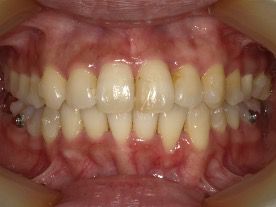

AFTER

30代 女性 叢生 AFTER

上下に叢生が見られる。歯列の拡大、臼歯の遠心移動、IPRを組み合わせてインビザラインで治療を行う事にした。

コンプライアンスが良く、治療に協力的だったため治療はスムーズに進んだ。